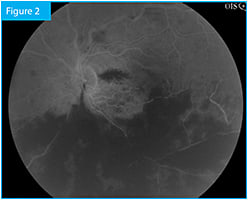

The patient is a 45-year-old otherwise healthy male who presented with sudden loss of vision in his left eye. Visual acuity OS was counting fingers inferiorly at 6 feet. Clinical exam and color fundus photography (Figure 1) revealed a hemiretinal vein occlusion, which fluorescein angiography confirmed (Figure 2). Central retinal thickness was 624 µm as measured by Spectralis SD-OCT (Heidelberg Engineering) (Figure 3).

Figure 2. Fluorescein angiography (4:37:16) at presentation.